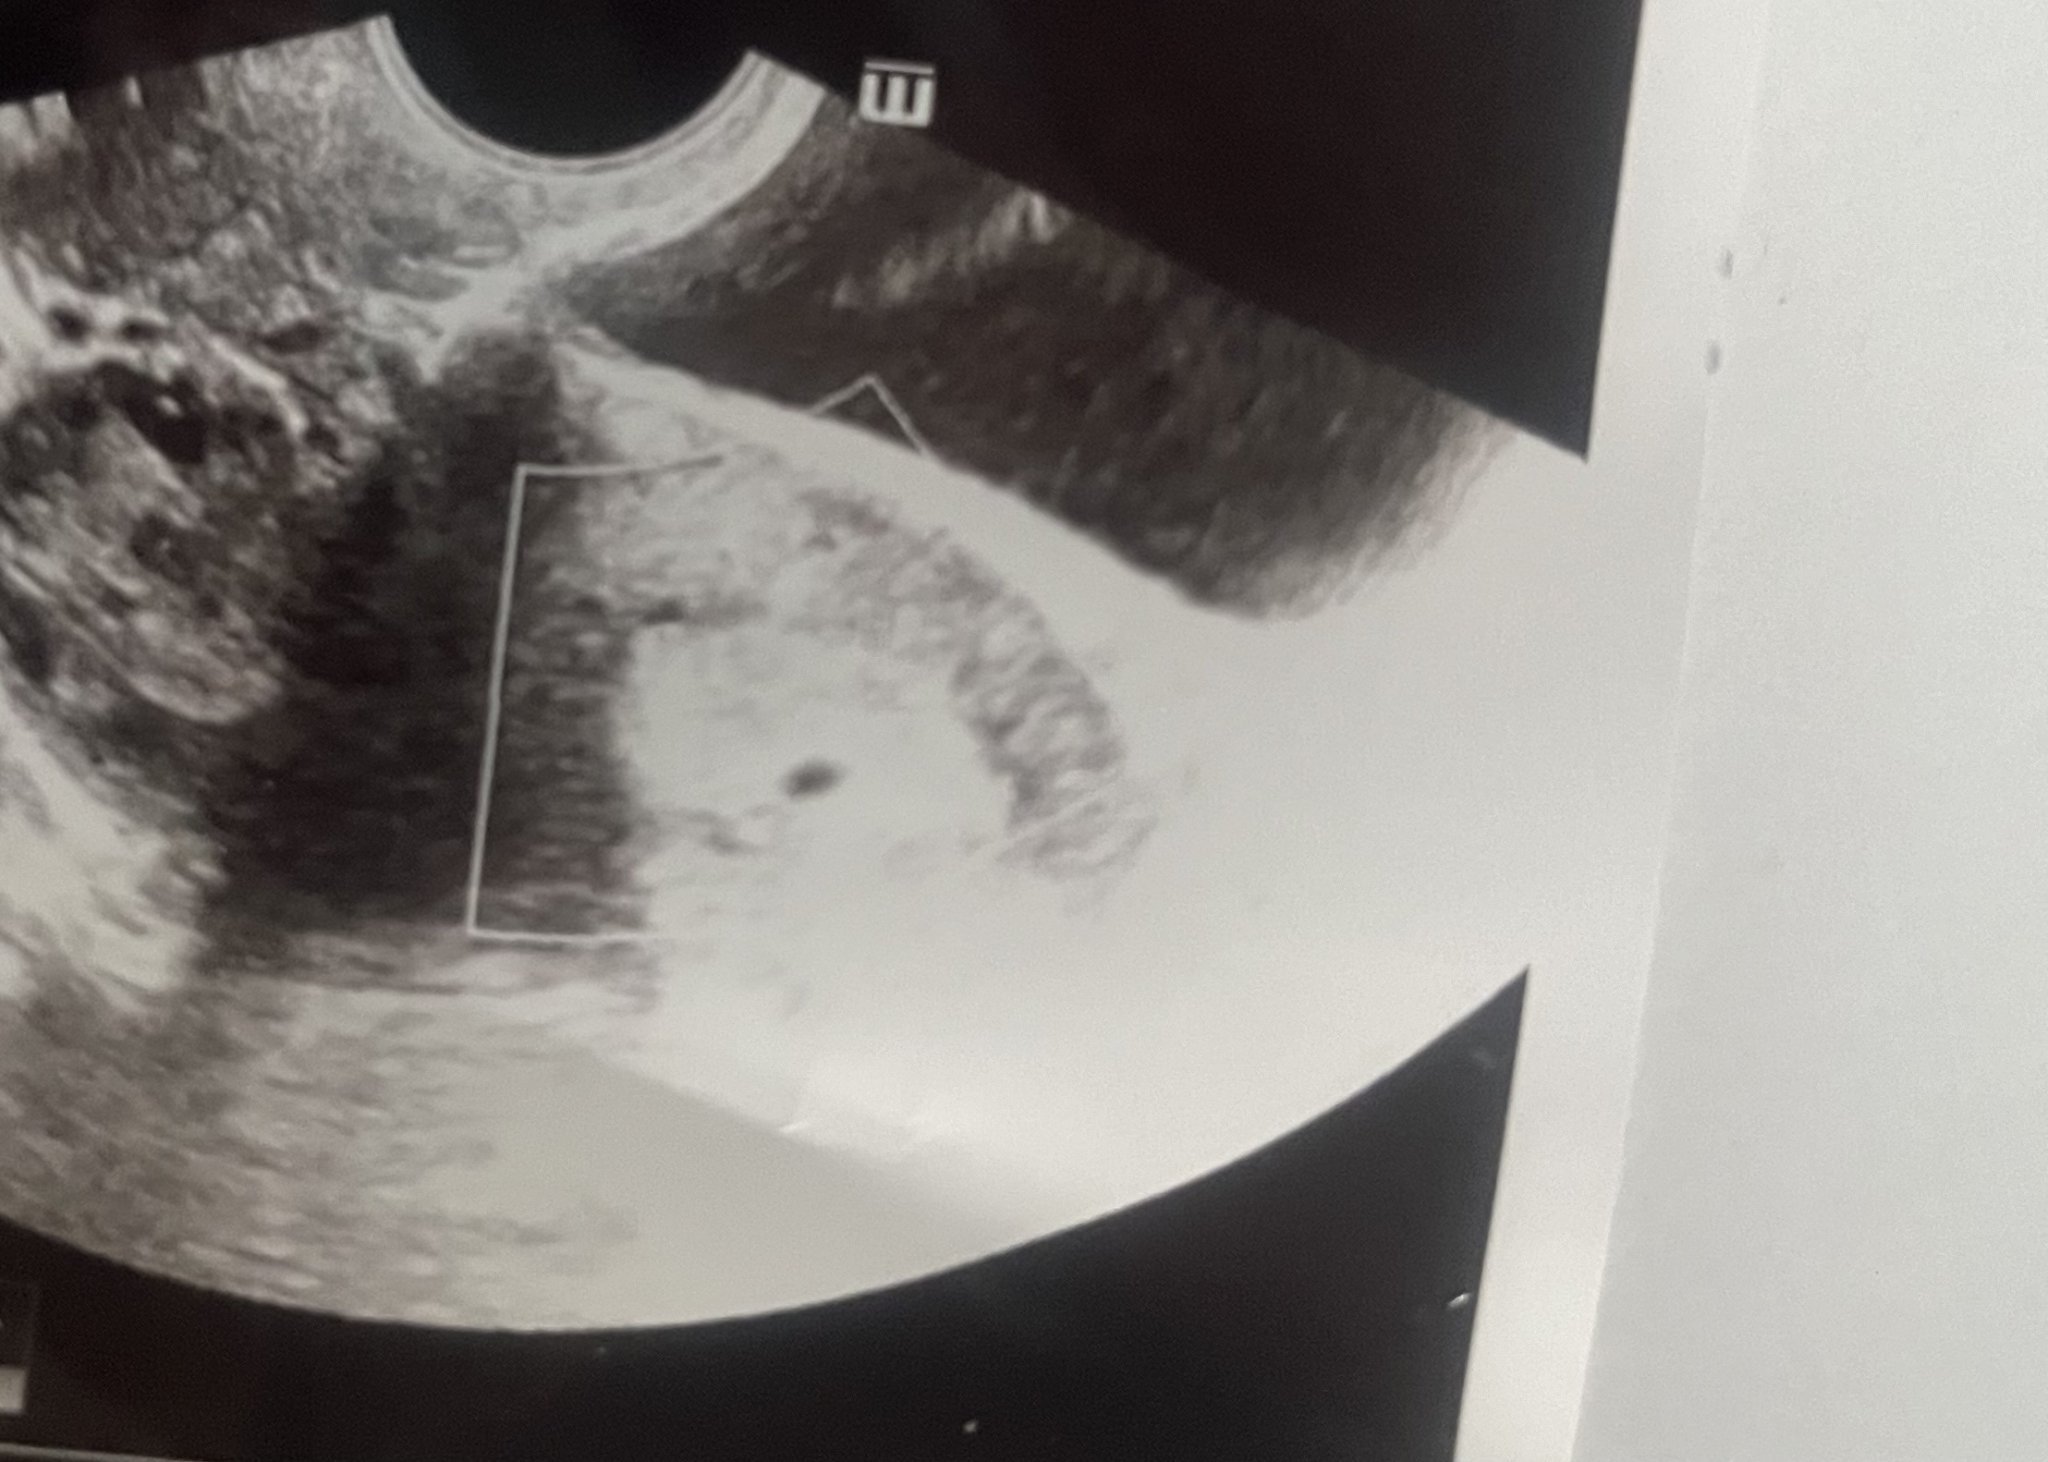

Какви са шансовете да запазите бременността и колко голямо може да бъде отлепването? Защо седмицата не е 7 седмици, както трябва да бъде, а 6 седмици?

Шансовете за поддържане на бременност са индивидуални и зависят от различни фактори, включително размера на отлепването. Отлепването може да варира значително в зависимост от обстоятелствата. Седмицата на бременността се определя въз основа на последната менструация, а не въз основа на датата на прегледа.